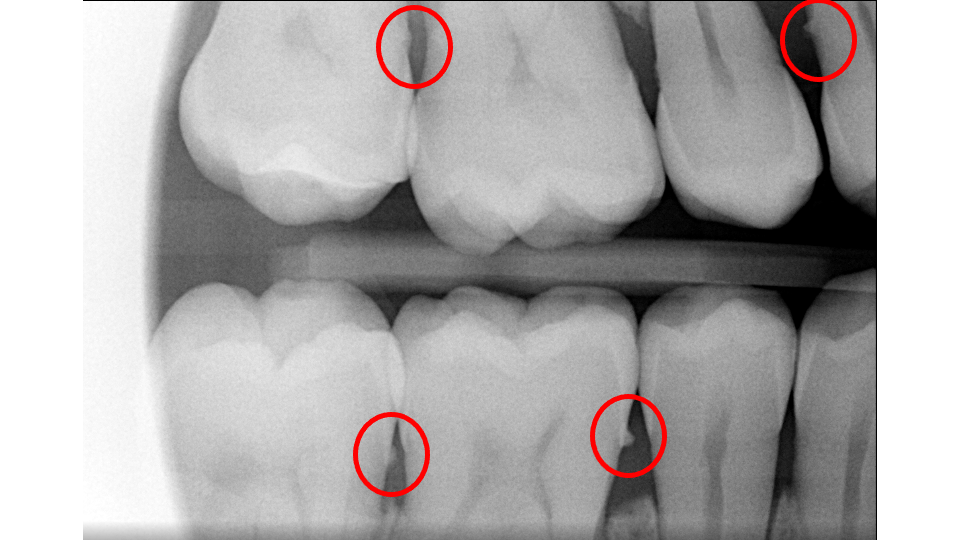

- Probing Depths: We gently measure the depth of the space between your gum and each tooth. In health, this pocket measures 1 to 3 mm. At this depth, bacteria can be 100% removed during cleanings and you can keep the area clean at home. Pockets of 4 to 5 mm are "borderline"; we can typically remove about 60 to 70% of bacteria, usually enough to stop bone loss, though these sites need close monitoring. Pockets of 6 mm or deeper are at severe risk, as most bacteria cannot be reached non-surgically.

- X-Rays (Radiographs): X-rays show the pattern and extent of bone loss. We can see whether bone has been lost evenly (horizontal loss) or whether craters and vertical defects have formed. This pattern directly determines which type of treatment you need.